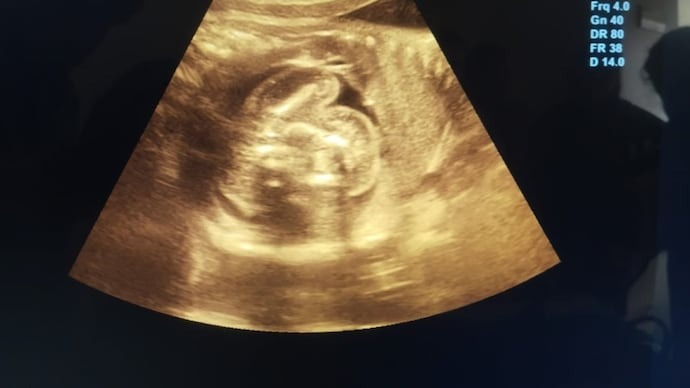

Emma’s pregnancy had progressed without complications. Regular checkups, ultrasounds, and prenatal care showed no signs of irregularities. So when her labor began two weeks before her expected due date, she and her husband, Mark, weren’t particularly concerned.

Upon arriving at the hospital, Emma was admitted for monitoring. While reviewing her latest ultrasound, doctors noticed something unusual: a second, smaller amniotic sac adjacent to the main one. Confused and intrigued, the medical team prepared for what they assumed was an unusual presentation of twins.

As the delivery began, doctors carefully navigated the birth of Emma’s healthy baby girl. However, what followed next left the entire team stunned. Inside the secondary sac was what appeared to be an underdeveloped fetus that had stopped growing early in gestation.

This rare occurrence, known in medical terms as “fetus in fetu,” happens when a twin embryo is enveloped by its sibling during the early stages of pregnancy. The enveloped fetus does not develop fully and typically remains undetected unless it causes complications or is discovered incidentally.

Fetus in fetu is an extremely rare condition, estimated to occur in less than 1 in 500,000 live births. Unlike conjoined twins, where both fetuses grow simultaneously and are partially fused, fetus in fetu involves one fetus becoming encapsulated within the body or womb of the other. In most cases, the underdeveloped fetus is discovered during infancy or early childhood, usually as a mass in the abdomen.

However, in Emma’s case, the discovery happened at birth, making it even more uncommon. The encapsulated fetus had its own amniotic sac and had stopped developing several months into the pregnancy. It posed no risk to Emma or her baby and was removed safely during the delivery procedure.